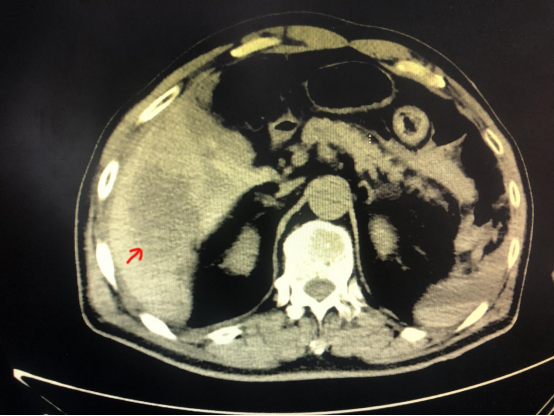

CT所示血管瘤位置

“肝血管瘤破裂出血非常凶险,患者必须紧急手术否则挺不过今晚。”在迅速评估周先生病情后,肝脏外科林汉教授迅速准备,在ICU、麻醉科、手术室的全力配合下当即为周先生进行了急诊剖腹探查手术。周先生腹腔内已经出血2000余ml,相当于他体内总血量的一半。林汉教授仅用不到两个小时就控制住出血,并将破裂的肝血管瘤切除。